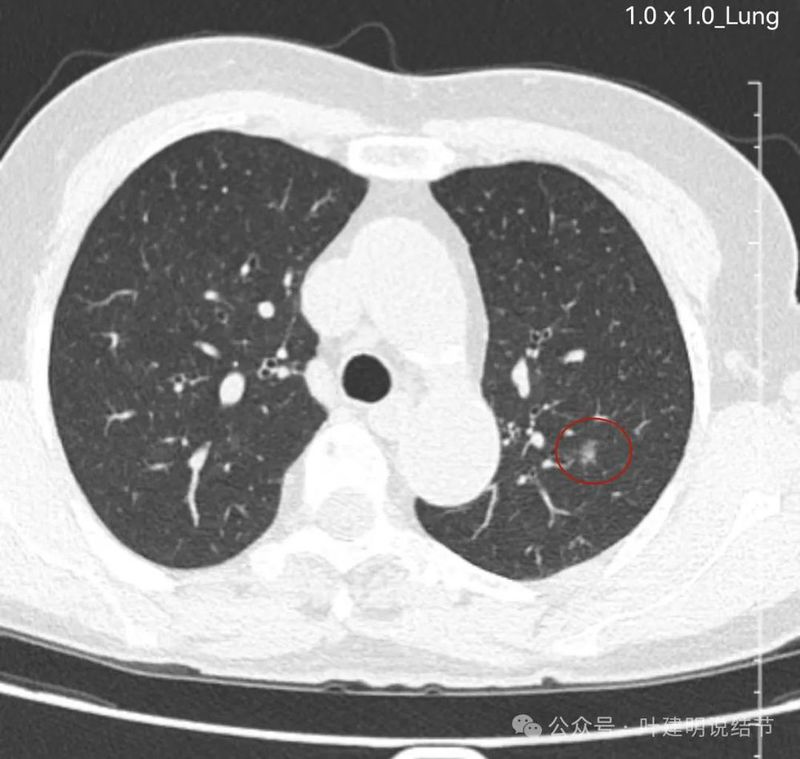

左下实性结节,明显有膨胀感,边缘虽然光滑,但给人感觉不舒服,恶性的可能性大些。